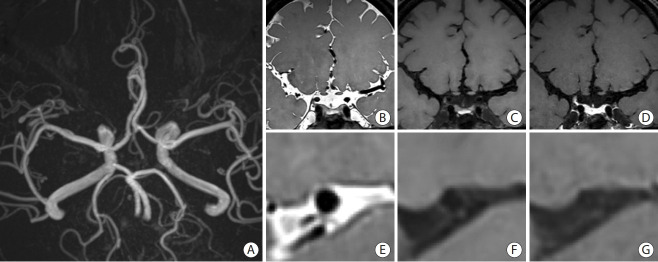

Intracranial arterial disease (ICAD) is a heterogeneous condition characterized by distinct pathologies, including atherosclerosis. Advances in magnetic resonance technology have enabled the visualization of intracranial arteries using high-resolution vessel wall imaging (HR-VWI). This review summarizes the anatomical, embryological, and histological differences between the intracranial and extracranial arteries. Next, we review the heterogeneous pathophysiology of ICAD, including atherosclerosis, moyamoya or RNF213 spectrum disease, intracranial dissection, and vasculitis. We also discuss how advances in HR-VWI can be used to differentiate ICAD etiologies. We emphasize that one should consider clinical presentation and timing of imaging in the absence of pathology-radiology correlation data. Future research should focus on understanding the temporal profile of HR-VWI findings and developing quantitative interpretative approaches to improve the decision-making and management of ICAD.